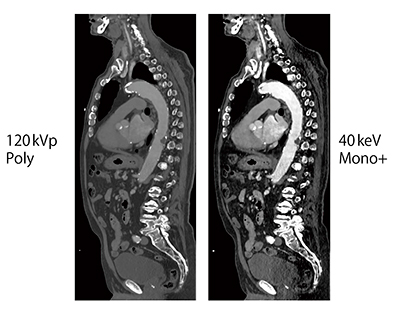

Case3は,77歳,血中クレアチニン値の高いTAVI適応症例である。本症例における使用造影剤量は,大動脈全体で15mLであり,それを50%に希釈しているため120kVpでは画質が低下するが,Monoenergetic Plusの40keV画像では,TAVIの治療計画を立てる上で十分な画質が得られている(図3)。

図3 Case3:77歳,血中クレアチニン値の高いTAVI適応症例のMonoenergetic Plus画像(造影剤量15mL)